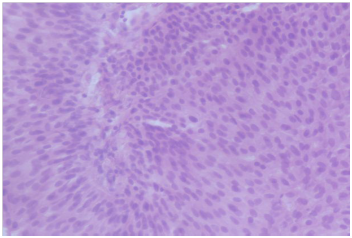

The patient was then planned for a partial penectomy along with transurethral resection of the bladder tumour. The patient underwent a partial penectomy (Figure 3) along with transurethral resection of the bladder tumour. The pathology results from the TURBT (Transurethral resection of bladder tumour) revealed a low grade transitional cell carcinoma, with no muscle invasion (Figures 4 & 5). Penile resection specimen showed a moderately differentiated squamous cell carcinoma with no lympho vascular invasion with the re-sected margin being negative for tumour (Figures 6 & 7). The TNM stage of the penile and bladder tumour was T1N0M0 and T1N0M0, respectively. The final diagnosis was double primary cancer of the penis and bladder. The follow-up check Cystoscopy and CT scan of the abdomen and pelvis done six months after the operation showed no evidence of recurrence. The inguinal lymphadenopathy too subsided post-operative lyon antibiotics treatment, presumably being reactive in origin. Patient reports no lower urinary tract symptoms and has good stream and minimal post void volume.8

Figure 4 Low power magnification of penile growth.

Figure 5 High power magnification of penile growth.